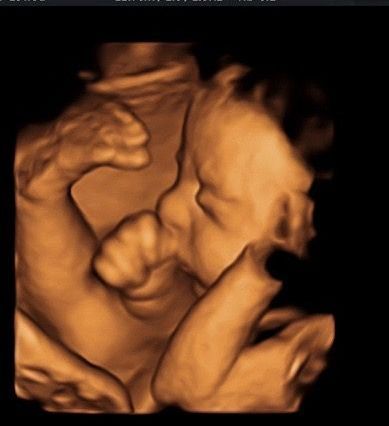

4D Scan لمتابعة جنينك أول بأول

عيشي تجربة مميزة مع تقني ة فور دي سكان وتفاصيله بدقة عالية، والاطمئنان على نموه في كل مرحلة من مراحل الحمل.فحص آمن،

صورة أوضح، ومتابعة لحظية تحت إشراف طبي متخصص لأن راحة بالك تهمنا

تابعي جنينك لحظة بلحظة مع ، دقة عالية، صور واضحة، واطمئنان مستمر على صحة الجنين بإشراف طبي.